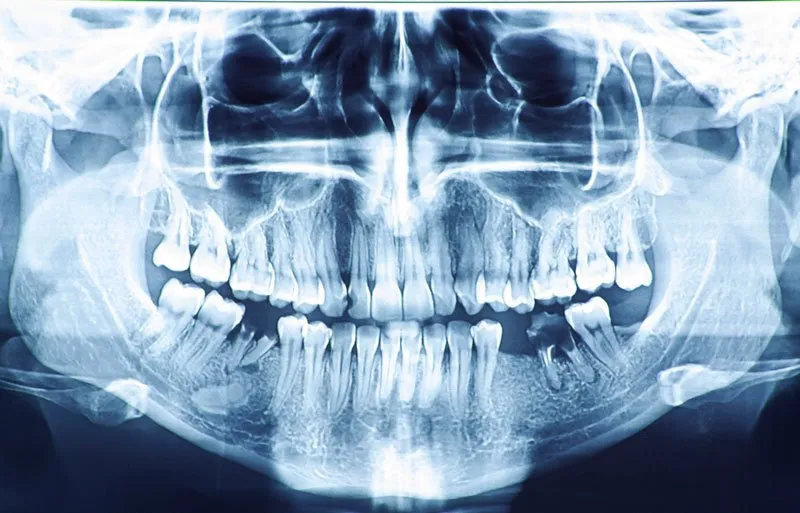

Chụp X-quang toàn cảnh răng cung cấp một cái nhìn tổng thể nhất về toàn bộ hệ thống răng miệng. Trong đó bao gồm cả răng khôn, hàm răng, xoang vùng mũi và khớp thái dương. Phương pháp này giúp bác sĩ chẩn đoán chính xác các tình trạng. Ví dụ như sâu răng, u nang, răng mọc lệch, hoặc răng ngầm. Việc có được cái nhìn toàn diện này sẽ giúp đưa ra các phương pháp điều trị hiệu quả. Đồng thời đưa ra phù hợp với từng trường hợp cụ thể. Từ đó hạn chế các rủi ro phát sinh trong quá trình điều trị.